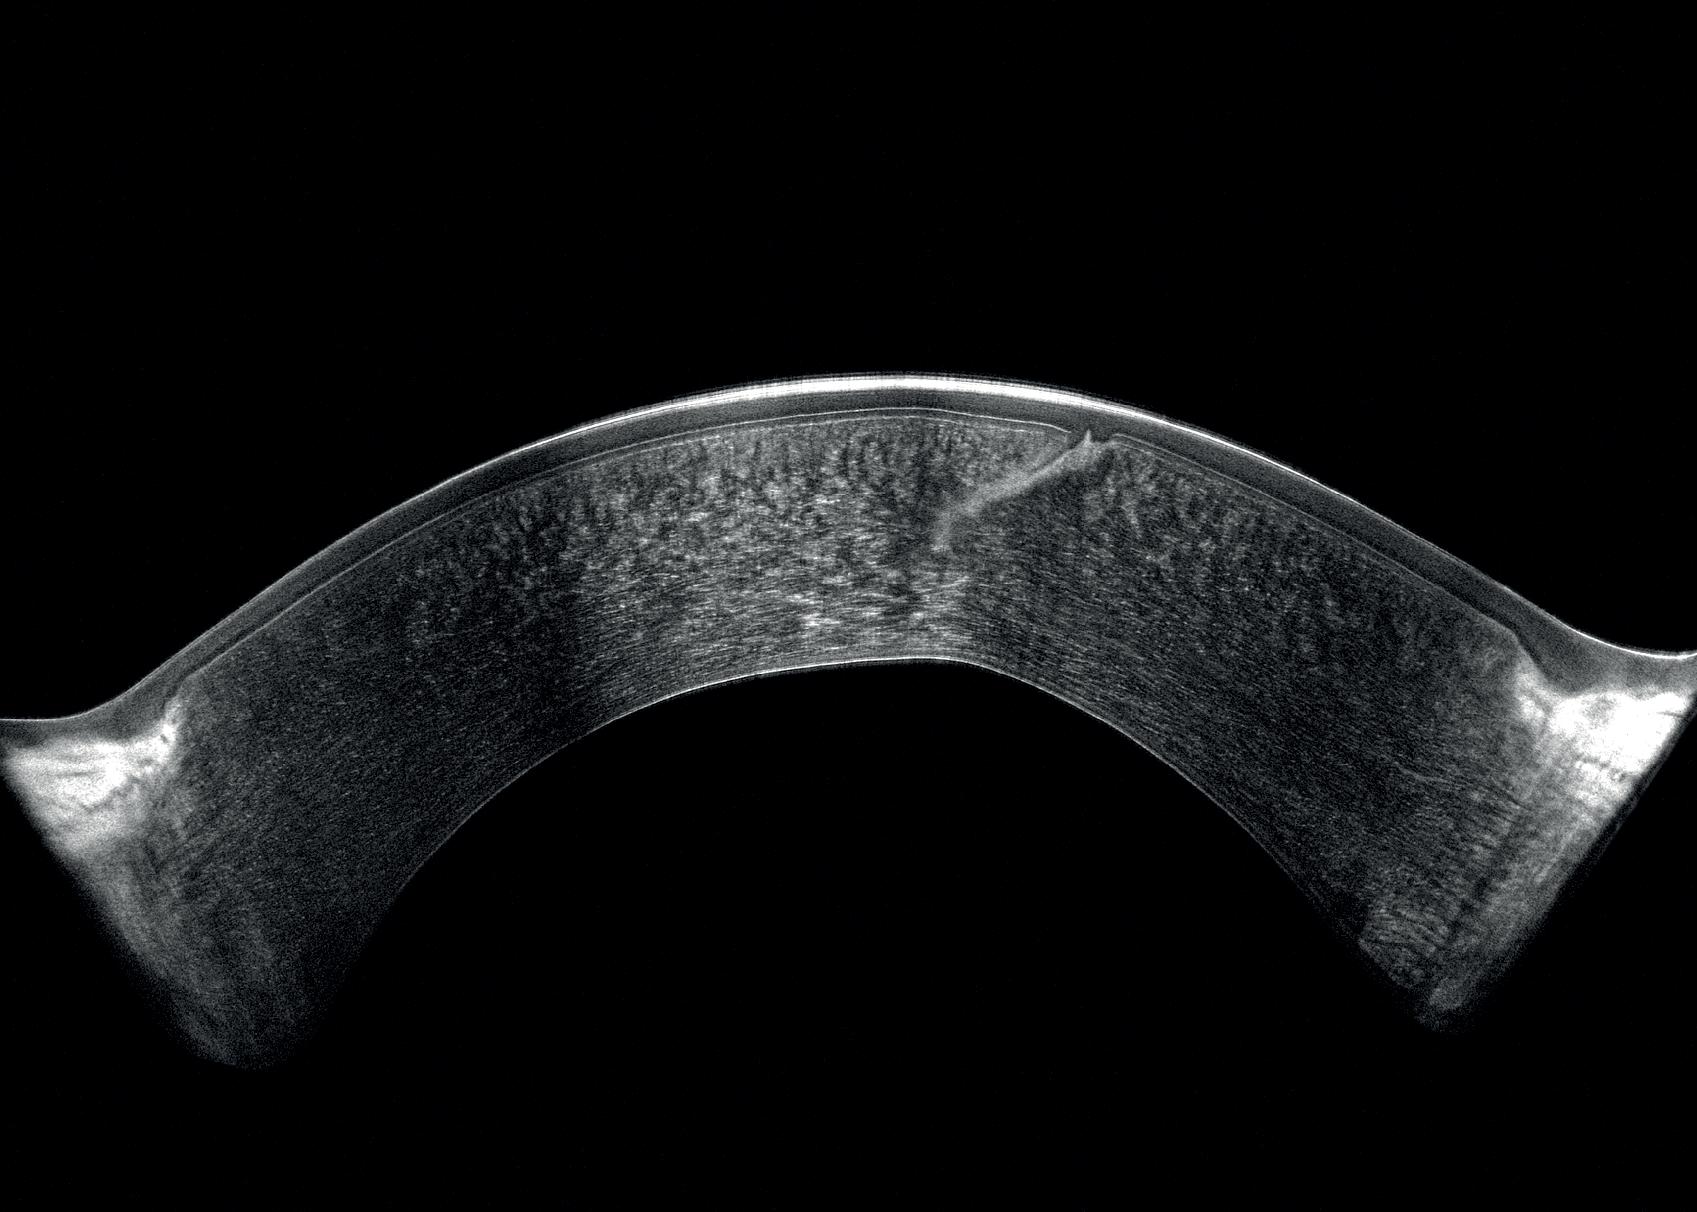

Figure 1. Correct positioning of iStent inject, two years after surgery, as shown by an anterior segment OCT (taken by Christelle Cochet).